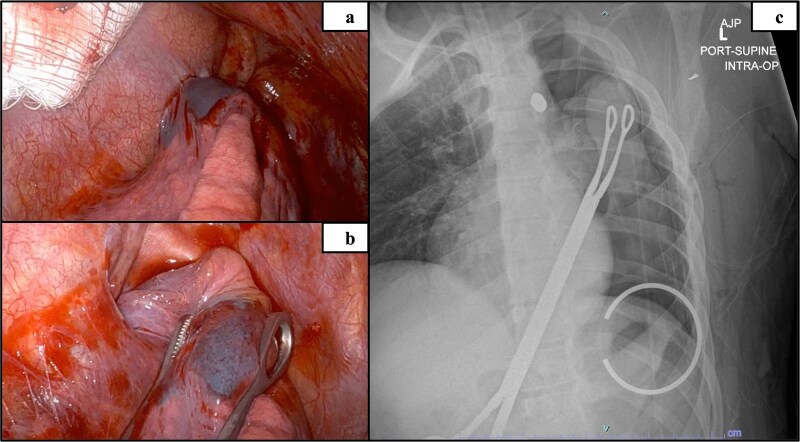

本病例研究报告了一名17岁的男性,在左上臂受枪伤后接受了机器人辅助的异物取出术,该枪伤导致子弹穿过胸壁直接停在主动脉肺窗处的纵隔。异物靠近大血管给术前成像和手术计划带来了挑战,因此成为这个独特病例的焦点。最终,机器人辅助取出子弹的手术成功了,没有损坏周围的结构。到目前为止,还没有关于机器人在这个解剖部位进行异物清除的研究报道。

This case study reports on a 17-year-old male that underwent robotic assisted foreign body removal after sustaining a gunshot wound to the left upper arm that resulted in the bullet traversing through the chest wall to stop directly in the mediastinum at the aortopulmonary window. The proximity of the foreign body to the great vessels introduced challenges for preoperative imaging and surgical planning, thus becoming the focus of this unique case. Ultimately, the robotic-assisted removal of the bullet was successful without damage to the surrounding structures. To date, no known study has reported on robotic foreign body removal at this anatomic location.